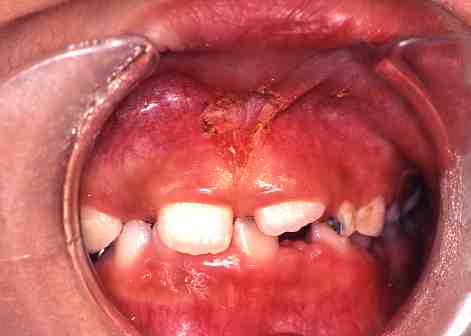

(3)小帯切除

1.術前

上唇小帯のスジが

張っています。

この症例は麻酔をして

レーザーにて切除しました。

出血はまったくありませんでした。